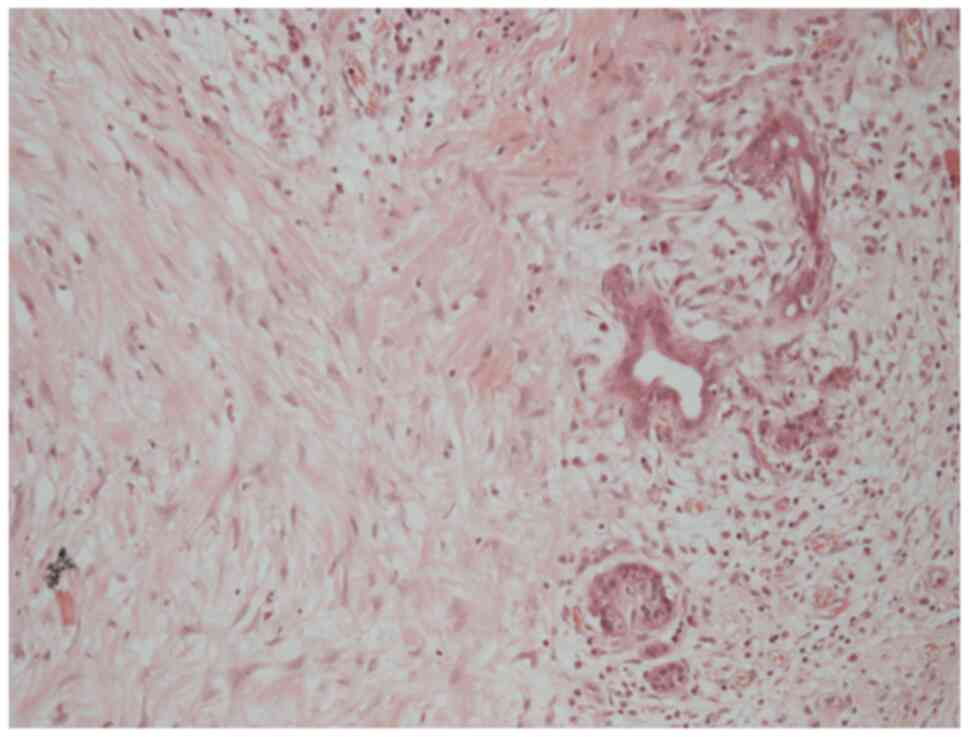

In July 2023, PET imaging revealed a new FDG-avid lesion in the anterior rectus sheath. Diagnostic biopsy was performed with histology again confirmed metastatic hCCA. The patient began systemic palliative chemotherapy. The patient began systemic palliative chemotherapy with gemcitabine (1,000 mg/m2 on days 1 and 8) and cisplatin (25 mg/m2 on days 1 and 8 of each 21-day cycle). By January, 2024, following eight cycles, surveillance imaging demonstrated increased uptake in a previously stable lung nodule. The rectus sheath metastasis and lung lesion were treated with surgical excision and microwave ablation, respectively. A new solitary lung recurrence was treated with ablation in October, 2024 (Figs. 8 and 9).

Axial computed tomography scan

demonstrating a right upper lobe lung metastasis (left panel),

subsequently treated with image-guided ablation (right panel).

Figure 8

Axial computed tomography scan demonstrating a right upper lobe lung metastasis (left panel), subsequently treated with image-guided ablation (right panel).

A histological examination of the rectus sheath deposit confirmed metastatic moderately differentiated adenocarcinoma, morphologically consistent with the patient s original diagnosis of hilar cholangiocarcinoma (Fig. 10). Histology was performed by the Department of Histopathology at King s College Hospital using routine paraffin-embedded sections, formalin fixation and standard diagnostic laboratory protocols.

Haematoxylin and eosin staining of the

rectus sheath metastasis, demonstrating moderately differentiated

adenocarcinoma (magnification, x100; no calibrated scale bar

available at source).

Figure 10

Haematoxylin and eosin staining of the rectus sheath metastasis, demonstrating moderately differentiated adenocarcinoma (magnification, x100; no calibrated scale bar available at source).